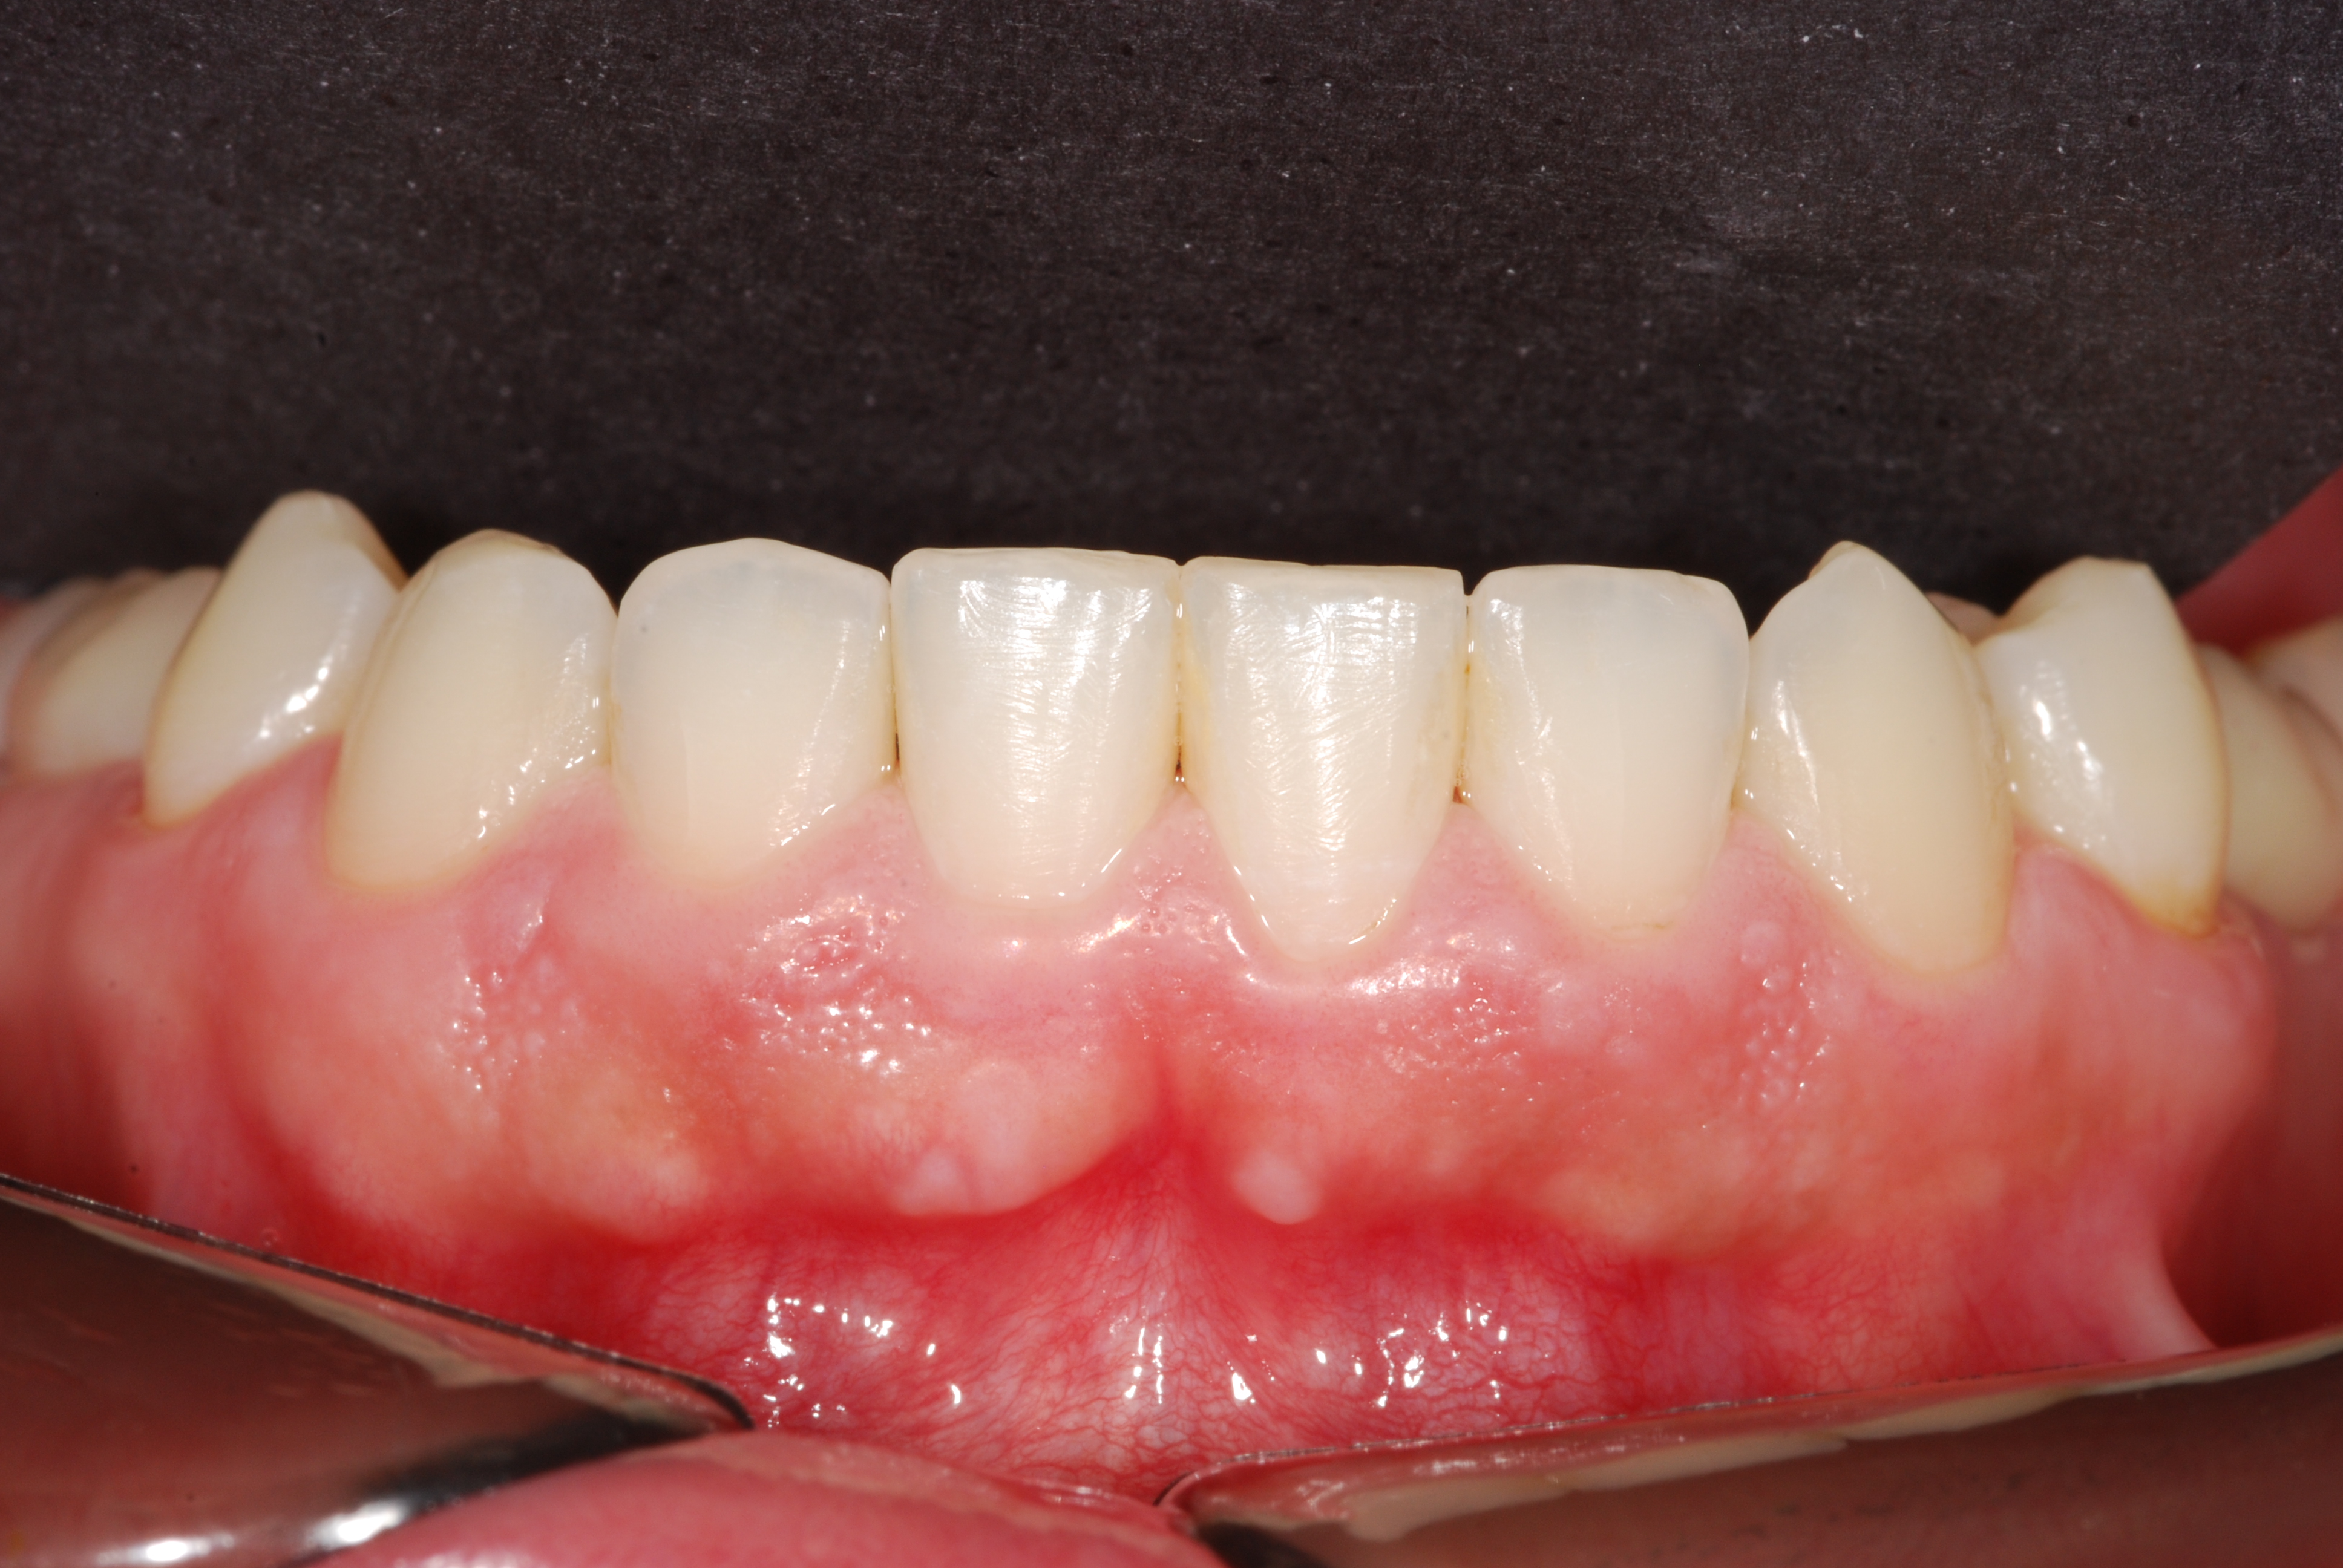

The presence of diastema, between anterior teeth, distorts a pleasing smile by concentrating the observer’s attention on the spaces. The patient’s needs and expectations must be considered in the process of treatment planning to ensure satisfaction with the treatment outcomes. There are many forms of therapy that can be used for diastema closure. A carefully developed diagnosis, which includes a determination of the causal elements and advanced treatment planning, allows the most appropriate treatment to be selected for each case. The aim of this paper is present a multidisciplinary approach as a solution to multiple diastemas in the anterior region using gingival tissue recontouring and direct adhesive restorations, with minimum wear of the dental structure, after the orthodontic intervention discussing the minimal intervention to obtain imperceptive and aesthetic final restoration. Thirty-six months after the treatment was carried out, the final aesthetic was maintained with all dental element details and gingival tissue harmony, without recurrence of periodontal pockets and the preservation of the tooth color and shape.